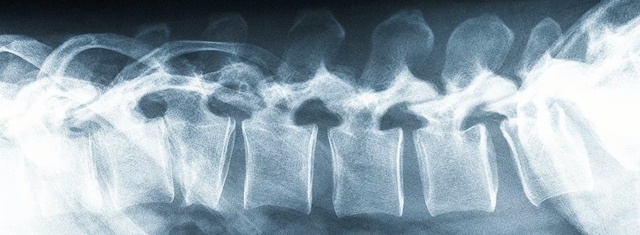

Best Video References: Fracture

Featured videos selected by a smart neural network algorithm